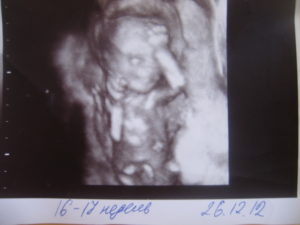

Женщина может получить протокол и фото результатов УЗИ на 16,17 неделе беременности. На основании данных врач формирует биофизический профиль плода.

Плод свободно передвигается в амниотической жидкости. На крохотных ручках и ножках сформировались пальчики, которые мама сможет увидеть на фото УЗИ. Ребёнок демонстрирует великолепную мимику, рефлекторно гримасничая и улыбаясь. Зевающий малыш – прекрасный момент, который может запечатлеть фотография.

3Д фото плода